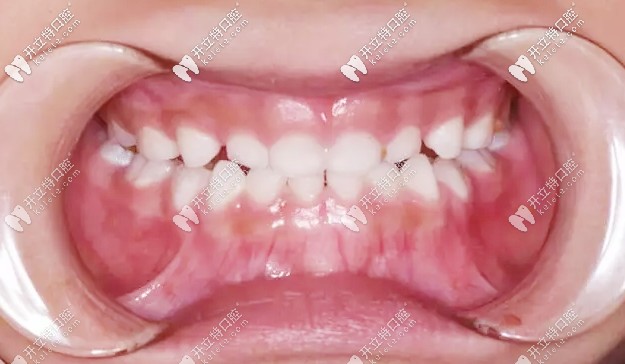

矯正前牙齒地包天

治療方案:選擇的是羅慕早期誘導(dǎo)干預(yù)矯正器,這是初期的石膏模型照片▼